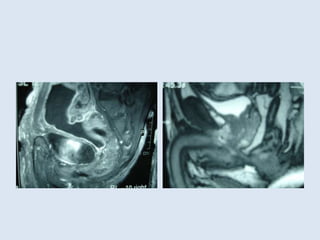

• On the other hand, the use of MRI for

preoperative staging of rectal cancer and the

circumferential resection margin had been

reported as compared to postoperative

Histopathology and recommended by AJCC,

NCCN and others as a routine preoperative

investigation of Ca rectum.

• Can we use MRI as an alternative tool to

classify rectal cancer?

• In other words can we have another added

value from the recommended preoperative

MRI?

• In the era of routine preoperative staging

using MRI where the Peritoneal reflection can

be accurately located in each individual

patient irrespective to his stature and BMI

using T2 weighted image, Ca rectum can be

reclassified preoperatively as: